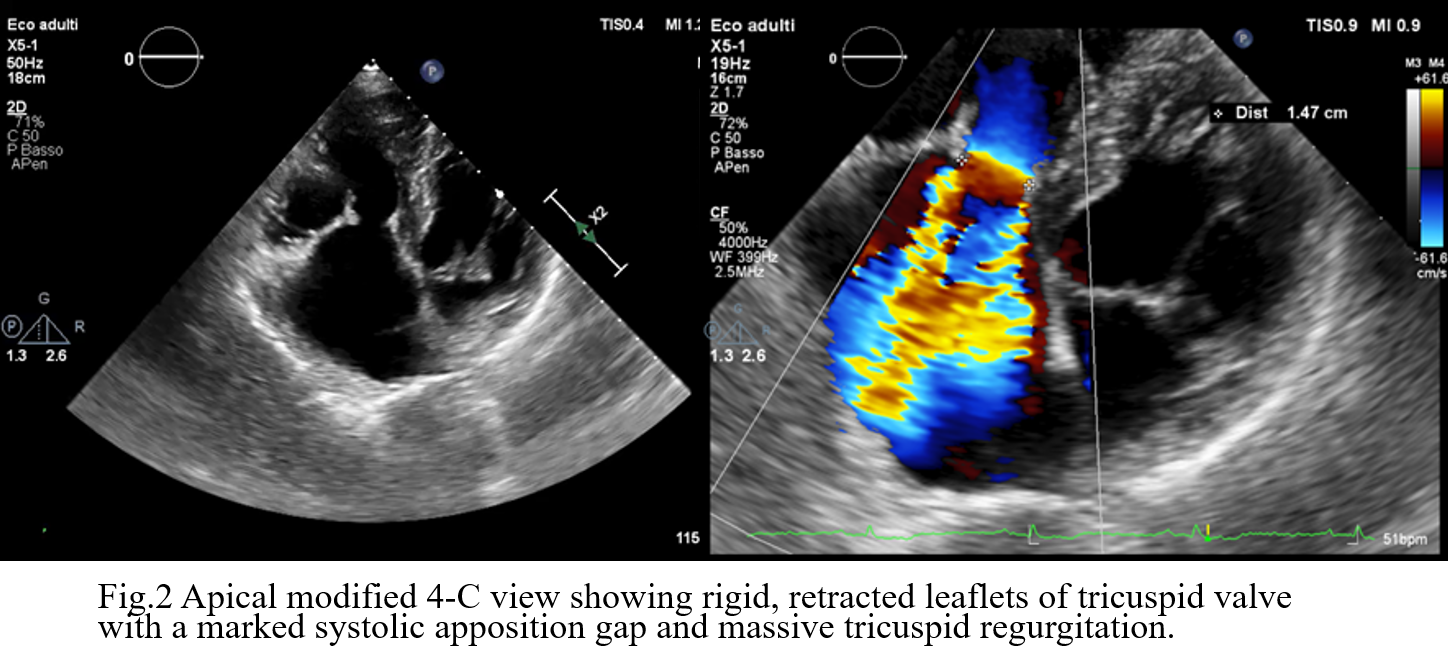

Background: Carcinoid Heart Disease (CHD) is a rare but ominous complication of neuroendocrine tumors (NETs), characterized by fibrotic plaque deposition on endocardial surfaces. While tricuspid valve involvement is well-documented, the pulmonary valve is often overlooked despite its significant impact on right ventricular (RV) hemodynamics. Case Presentation: A 73-year-old male with an ileal NET and liver/peritoneal metastases, stable under lanreotide acetate for four years, presented with progressive dyspnea and peripheral edema. Initial transthoracic echocardiography (TTE) and cardiac MRI identified severe tricuspid regurgitation (TR) and significant right heart dilation. The patient was referred to our Department to explore the feasibility of transcatheter tricuspid intervention. Advanced Imaging Findings: Comprehensive TTE and transesophageal echocardiography (TEE) confirmed RV dilation (RVD1 49 mm, RVOT 44 mm) with preserved systolic function (TAPSE 22 mm, FAC 48%). The tricuspid valve exhibited classic CHD features: fibrotic, retracted, and rigid leaflets with commissural fusion. 3D echocardiography showed a fixed, oval-shaped orifice (1.6 cm²) that remained immobile throughout the cardiac cycle due to systolic-diastolic mobility restriction (Fig.1). This resulted in massive TR (VC 16 mm, ERO 1.6 cm², dense triangular CW Doppler profile and systolic flow reversal in suprahepatic veins, Fig.2) combined with tricuspid stenosis (mean gradient 5 mmHg). Crucially, detailed evaluation of the pulmonary valve revealed retracted cusps. Diagnosis of pulmonary regurgitation (PR) was challenging at Color Doppler but a multiparametric assessment detected severe PR (dense CW Doppler with rapid interruption due to a rapid rise of RV diastolic pressures with pressure half-time of 80 msec and PR index of 0,62, Fig.3). Conclusion: These findings are pathognomonic for CHD, where vasoactive substances (e.g., serotonin) induce endocardial fibrosis. In this case, the complex anatomy of the tricuspid valve, combined with significant pulmonary valve involvement, rendered the patient unsuitable for transcatheter correction. This case emphasizes that the pulmonary valve must be rigorously evaluated in CHD, with a multiparametric approach, as its involvement is a critical determinant of surgical vs. percutaneous strategy. Management in this case must involve a multidisciplinary Heart Team to balance surgical risks against oncological prognosis.